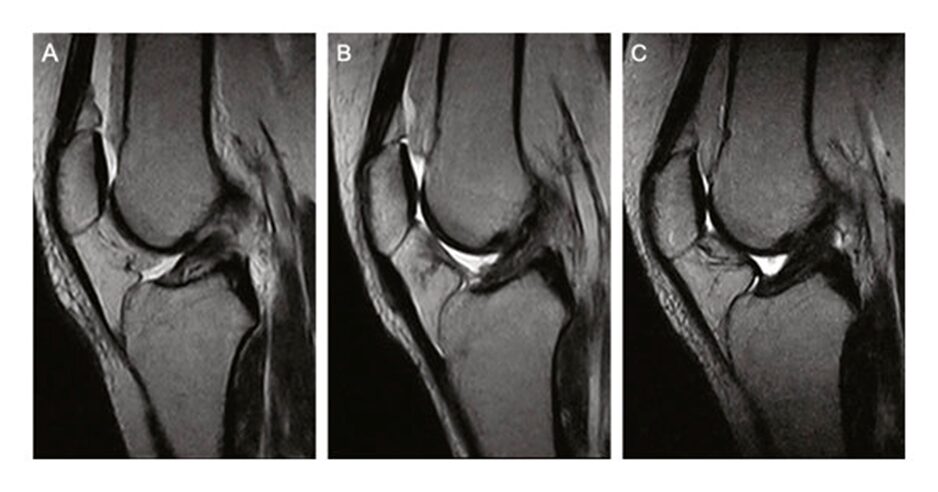

In solchen Fällen zeigt sich im MRT ein neu aufgebautes, belastbares Kreuzband.

In meiner Praxis zeigen sich in vielen Fällen dokumentierte Verläufe, bei denen nach entsprechender Behandlung im MRT wieder ein belastbares Kreuzband nachweisbar ist.

In meiner Praxis liegen dokumentierte Verläufe vor, bei denen sich nach der Behandlung nicht nur eine funktionelle Stabilisierung, sondern auch eine im MRT nachweisbare strukturelle Wiederherstellung des Kreuzbandes gezeigt hat.